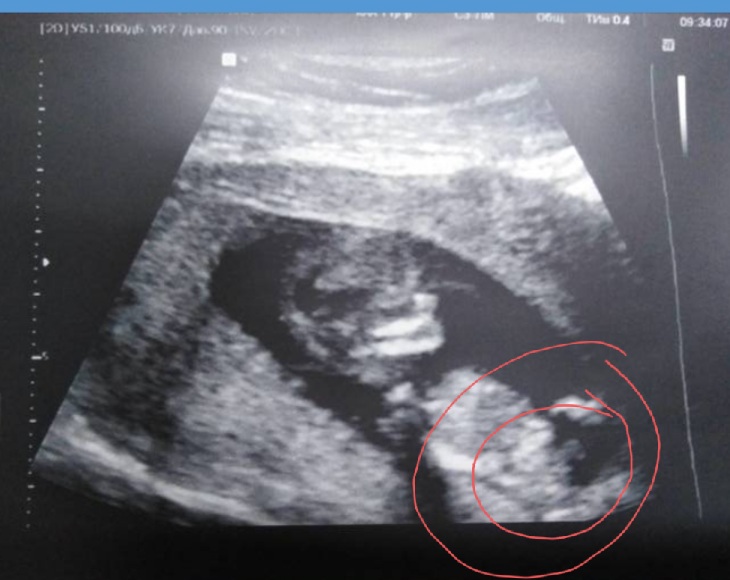

Катя

Ну это у вас ракурс просто удачнее, вот и видно лучше!

Вот тоже узи 12+2 и кстати мне тоже писали все что девочка...

Катя, господи, я перепроверила ваши записи, большинство вам писали что у вас больше похоже на мальчика. Так еще сюда фото выкинули неудачное.

Ну как по мне на этом фото тоже видно пиптик, или просто из-за того что у меня видео, я точно знаю куда смотреть...

вот так торчит у мальчиков.